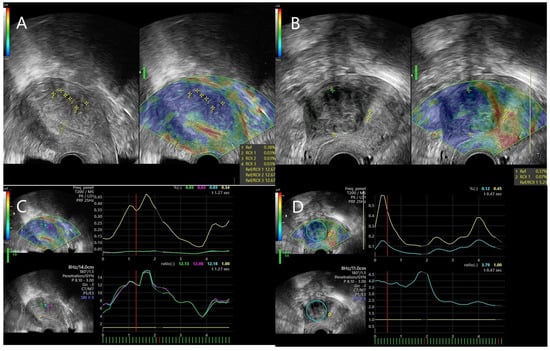

2.3. Strain Ratio Elastography Analysis

| Mean SR | 11.42 ± 1.87 | 5.20 ± 1.81 | <0.001 |

| Max SR | 13.43 ± 4.10 | 5.78 ± 2.08 | <0.001 |

| mean SR | 0.99 (0.97–1) | >7.71 | 100% (86.68–100%) | 96.23% (87.25–99.33%) | <0.001 |

| max SR | 0.98 (0.96–1) | >8.91 | 96% (80.46–99.79%) | 96.23% (87.25–99.33%) | <0.001 |